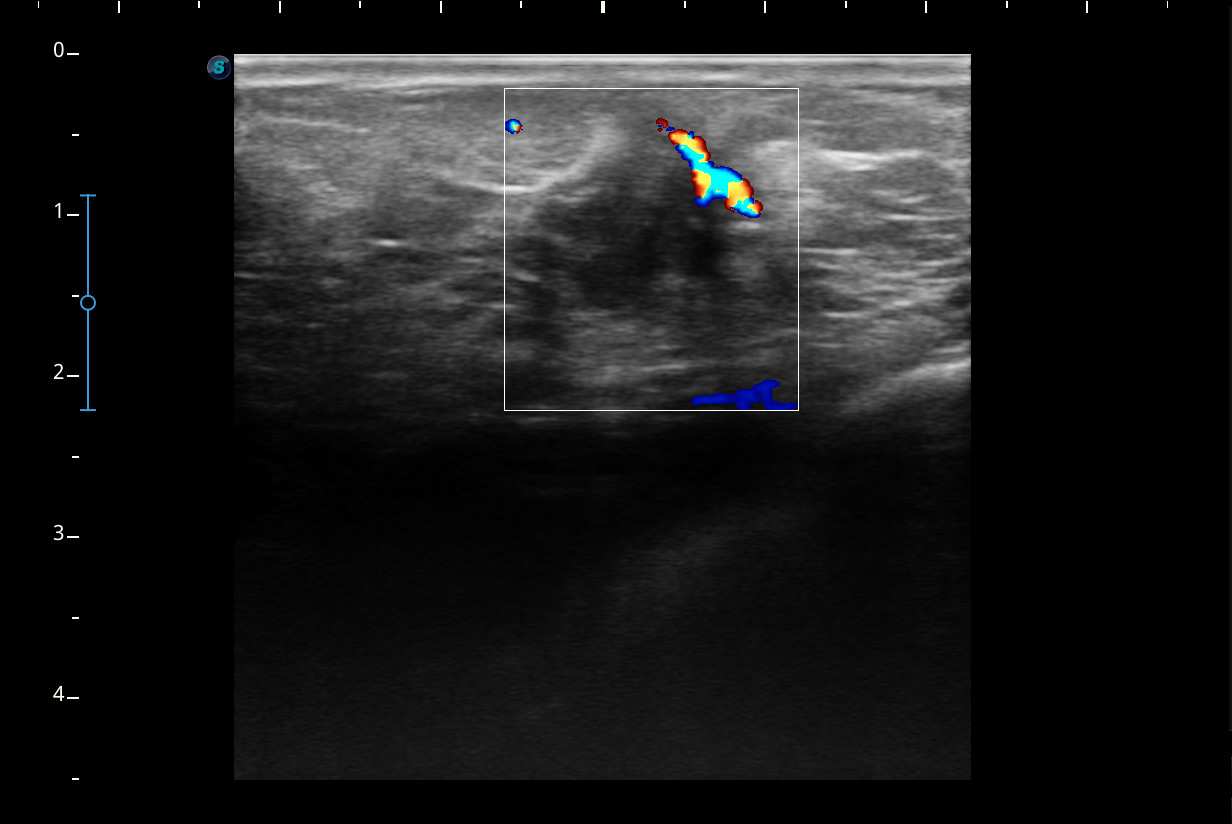

Hallazgos ecográficos

Se visualiza un nódulo mal delimitado, de bordes irregulares y algo espiculados, con captación doppler color sobre todo en periferia y posibles focos centrales de necrosis, compatible con posible neoplasia.